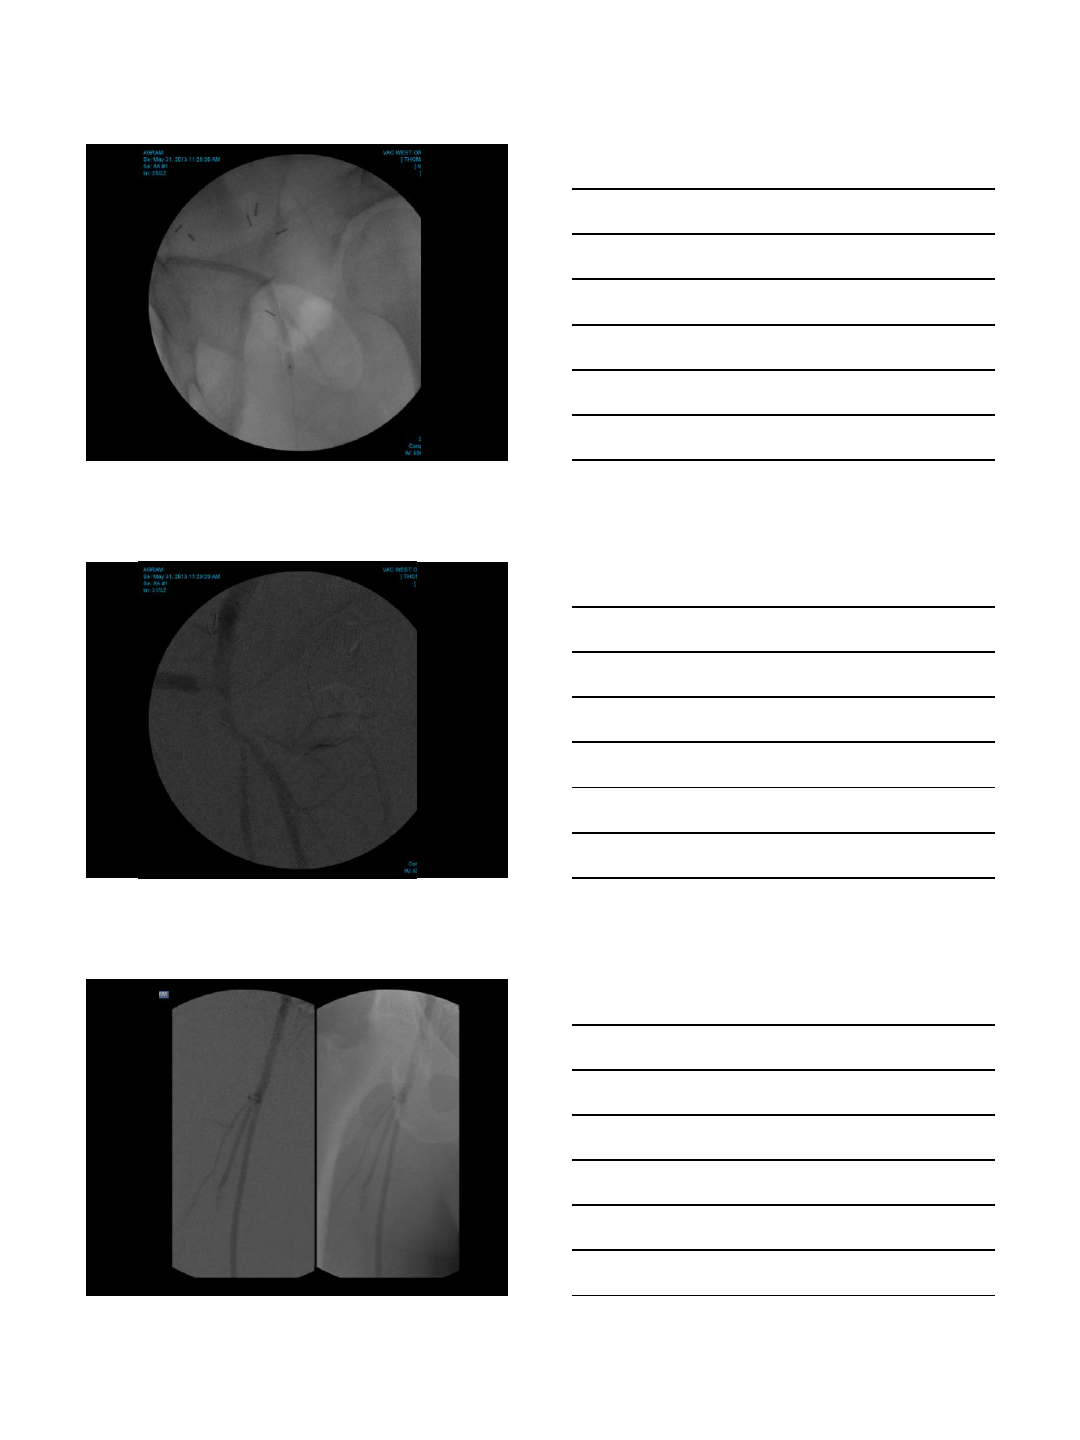

CO2 arteriogram and embolization

Aneurysm repair

•Iliac aneurysm coiling with CO2

•AAA stent-graft using CO2 & IVUS

•Total contrast used: 30 cc

•Renal function unchanged

CO2 Fistulogram

Dialysis access intervention

•This patient’s procedures are

completed whenever necessary without

the use of contrast medium

•No further allergic reactions